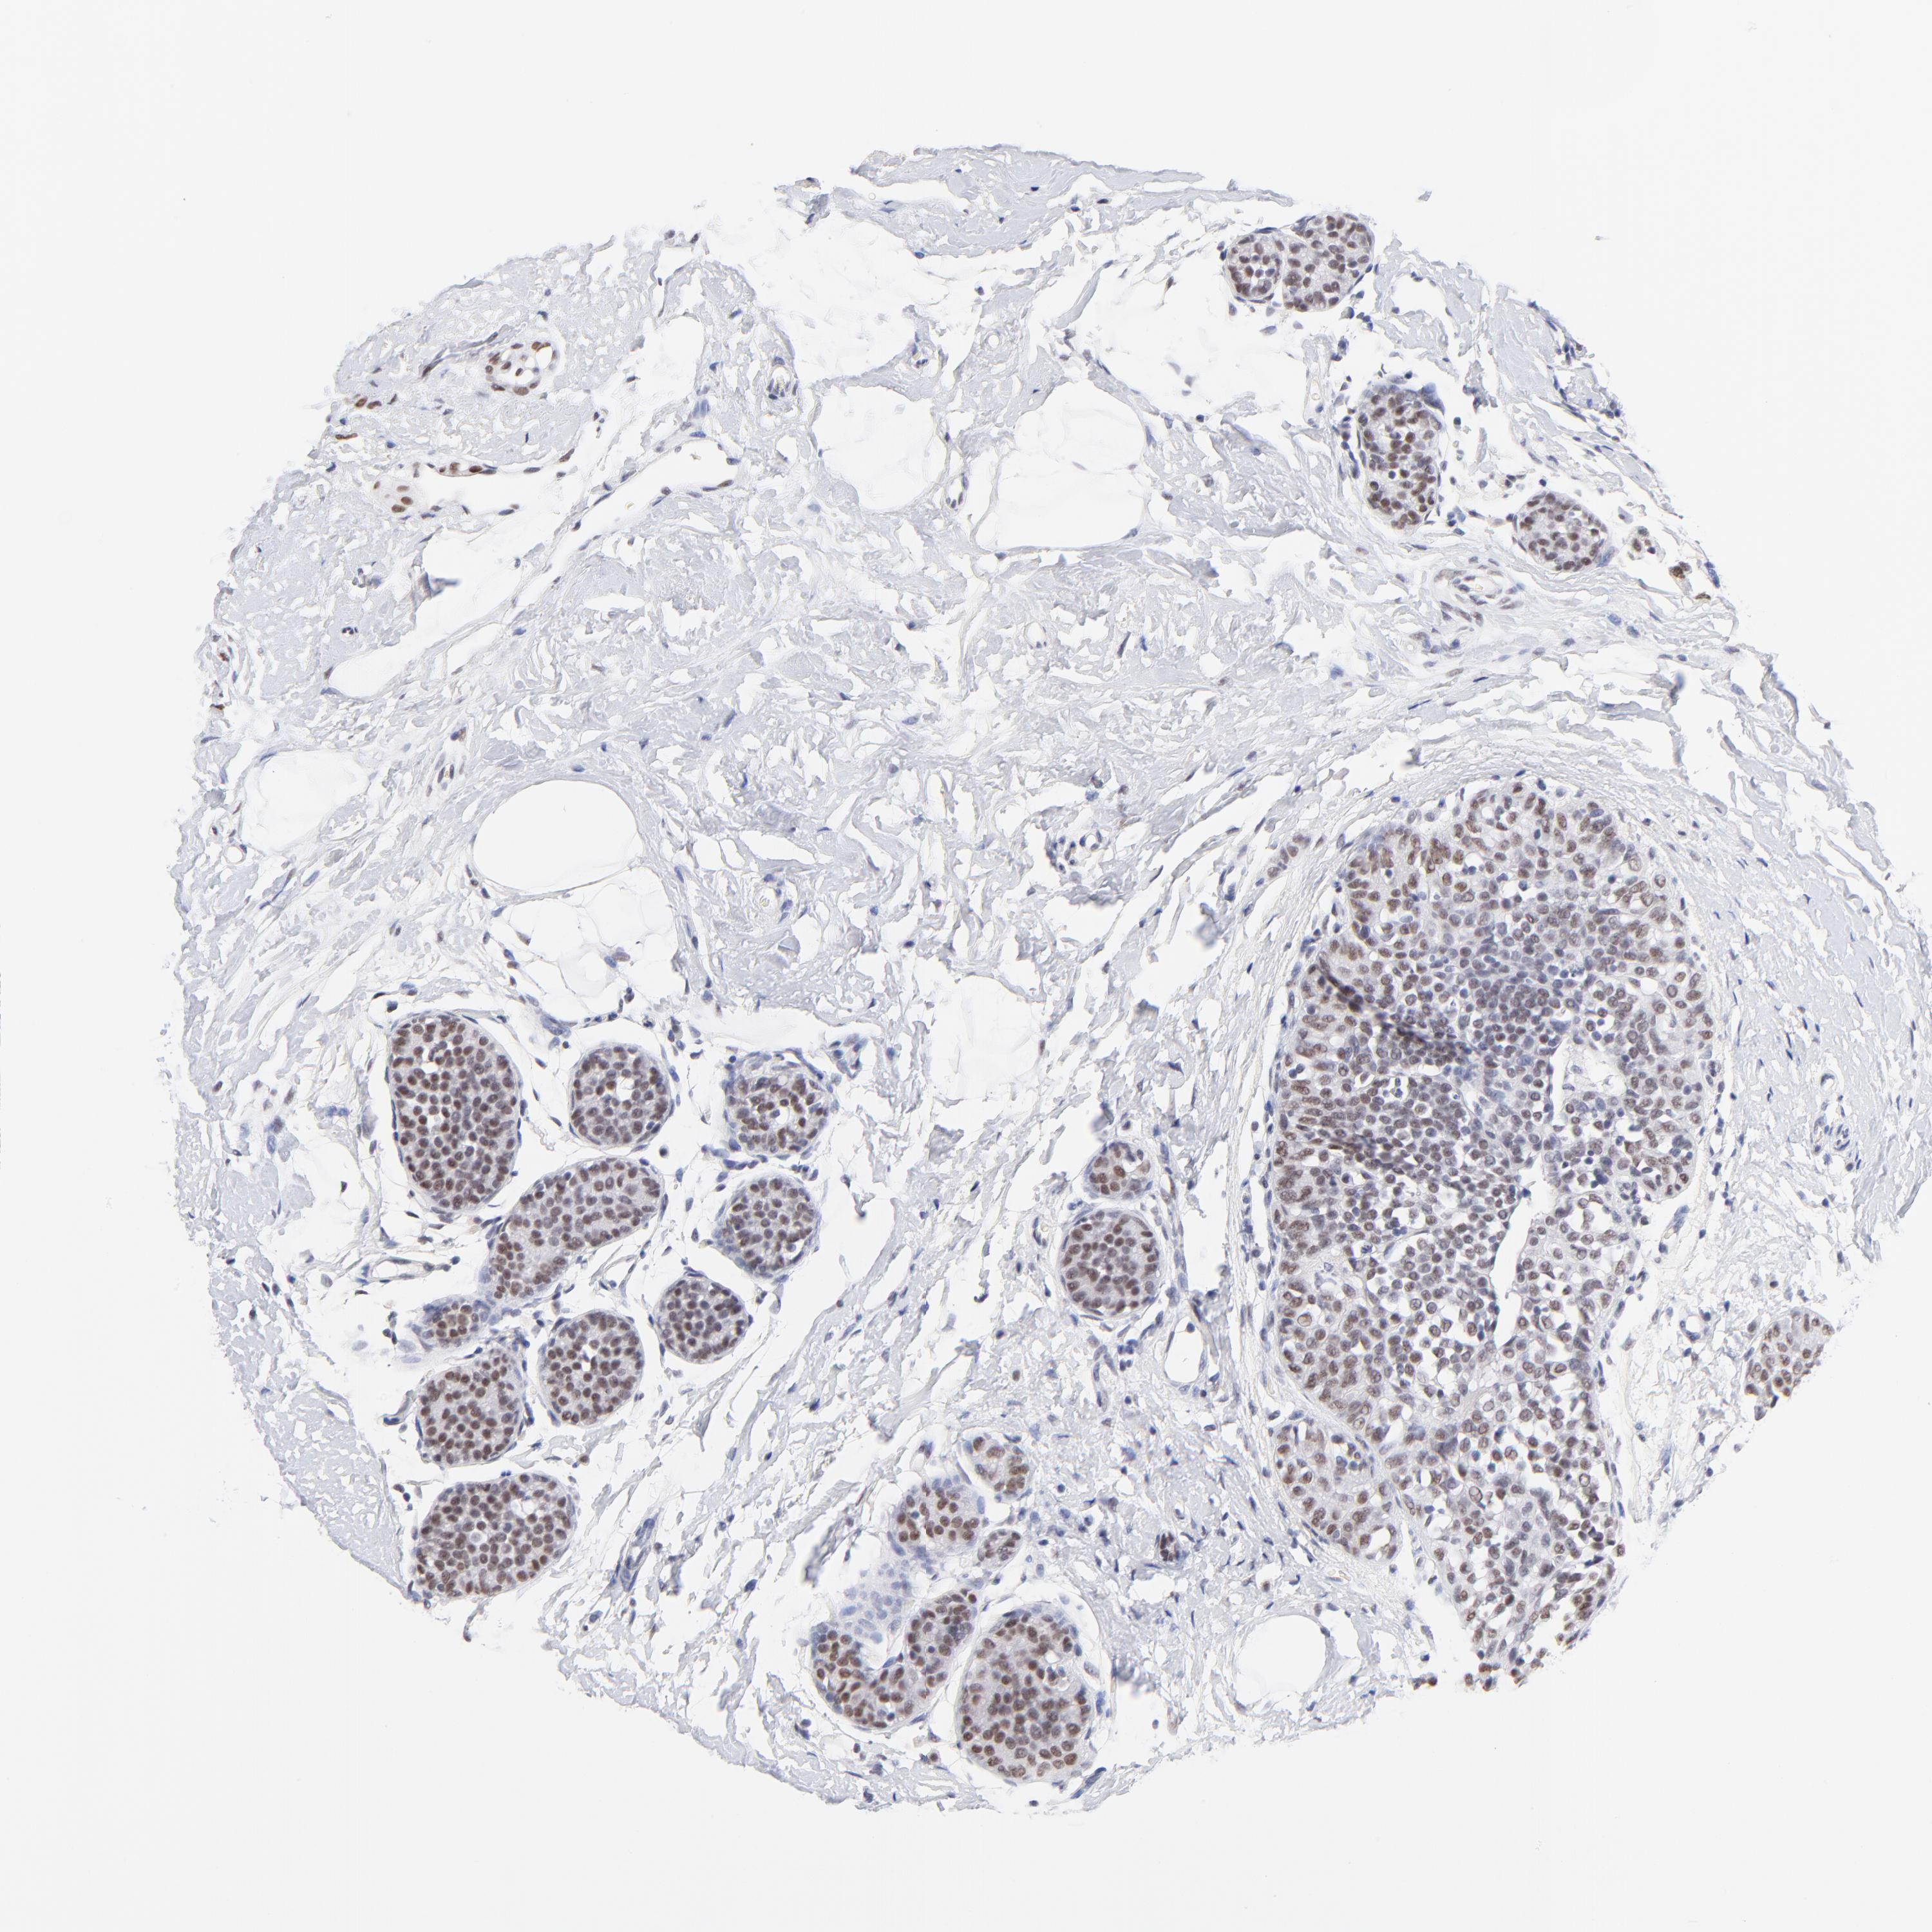

CANCER BREAST CANCER Show tissue menu

BRCA TCGA BRCA VALIDATION PROTEIN EXPRESSION

Breast cancer

Human cancer

Breast invasive carcinoma